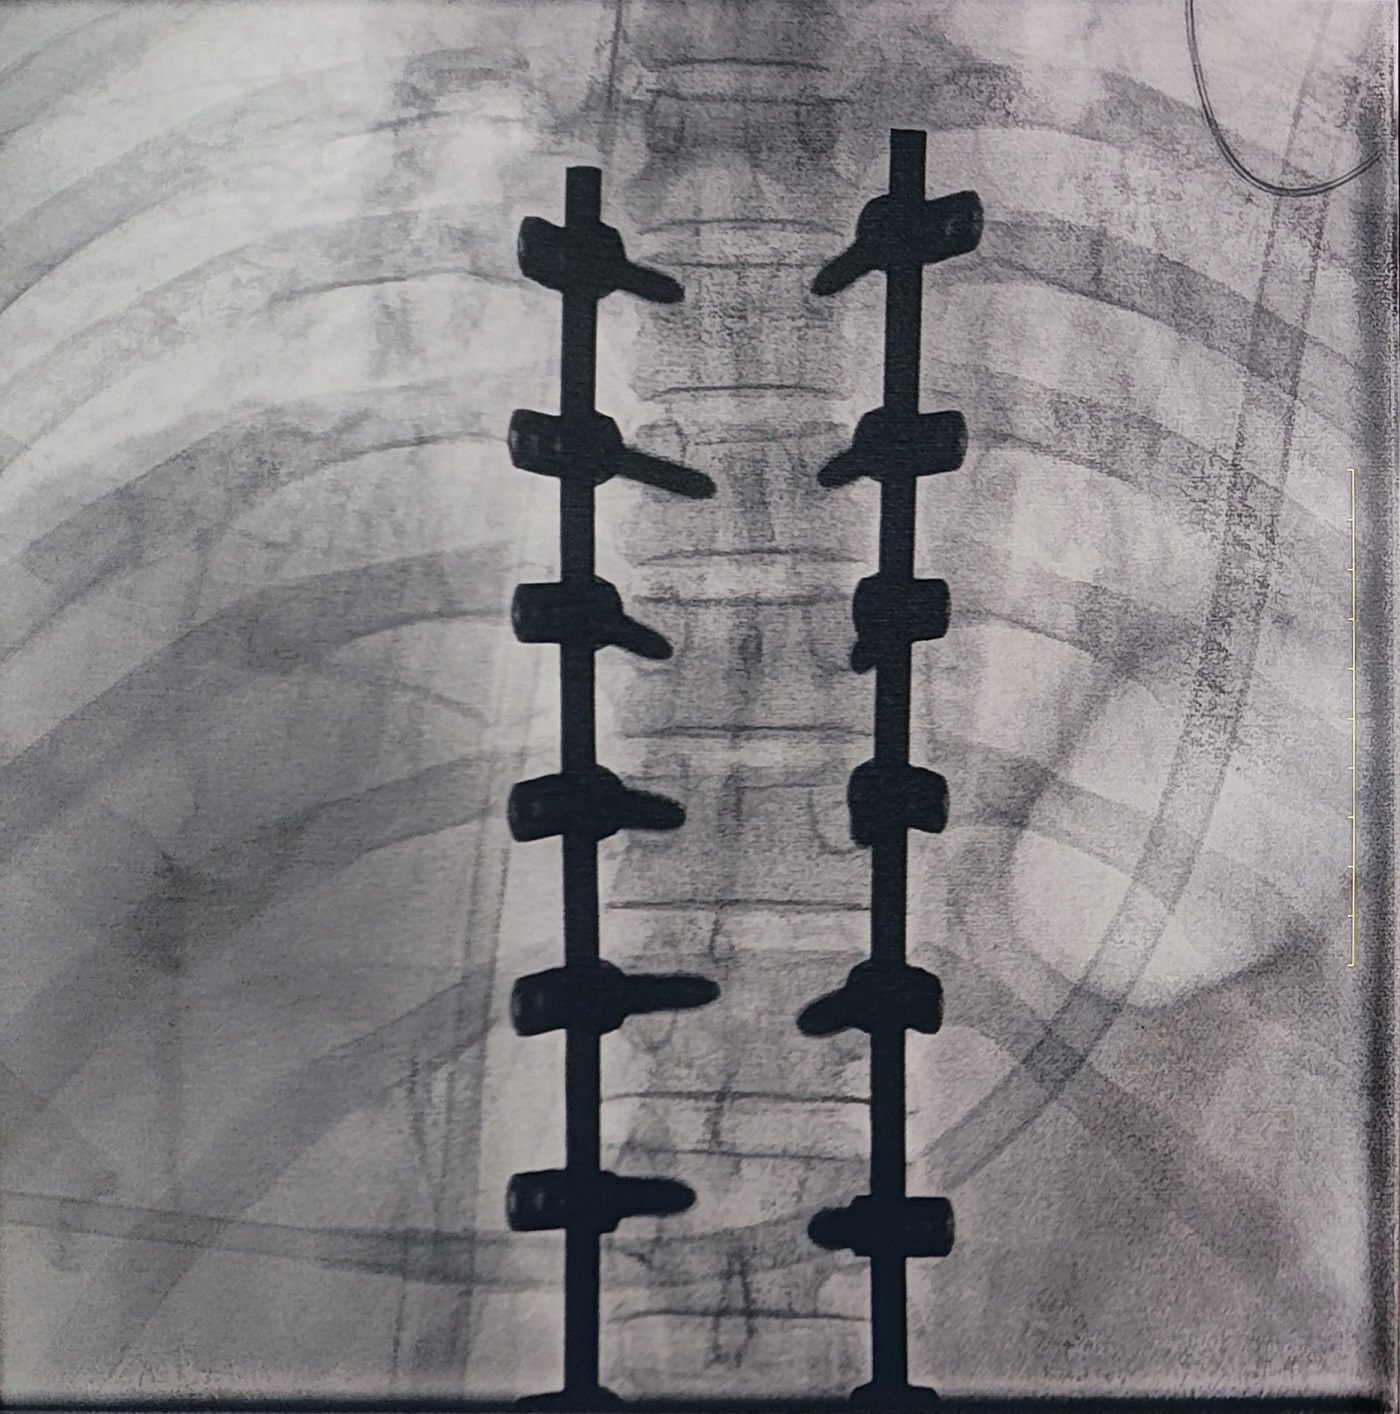

一場脊柱手術(shù)中,醫(yī)生需要拍攝跨越7個節(jié)段的脊柱影像,由于曝光的視野較大,常規(guī)視野的C形臂通常需要拍攝2-3次,普愛醫(yī)療大平板一體式C形臂30CM*30CM的“大視野”,輔助醫(yī)生一次性完成了7個節(jié)段的拍攝。最終,醫(yī)生在高清影像的輔助下完成了14枚螺釘?shù)木珳识ㄎ?、置入?/p>

大視野,不僅意味著醫(yī)生可以更快,獲取更全面的影像信息,做出精準判斷,無需多次拍攝定位,也顯著地降低了患者接受的輻射劑量。